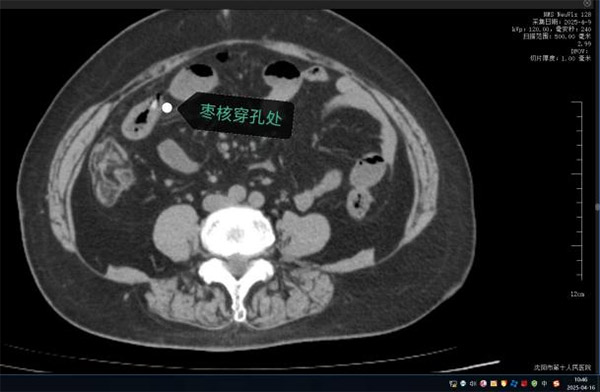

63岁的康阿姨因突发"刀绞般"的剧烈腹痛被深夜紧急送往沈阳市第十人民医院(沈阳市胸科医院)。短短数小时内,她已出现高热、腹肌强直等弥漫性腹膜炎症状,CT检查显示其腹腔内游离气体,高度怀疑消化道穿孔。追问病史时家属猛然回忆:今天上午康阿姨吃粽子时误将两颗枣核吞下!沈阳市第十人民医院(沈阳市胸科医院)普外科任庆华主任团队火速会诊,判断枣核尖端已刺穿小肠,必须立即手术。

凌晨的手术室里,任庆华主任与刘晓斌副主任医师打开腹腔时,眼前的场景令人心惊:大量浑浊脓液涌出,两枚长达3cm的尖锐枣核分别嵌顿在幽门处与回肠段,其中远端小肠已形成两处直径0.8cm的穿孔,两处约10cm及5厘米肠管因缺血呈黑紫色。医疗团队当机立断,行"胃切开异物取出术"完整取出胃内枣核后,针对坏死肠段实施精准的"小肠多节段部分切除术",同时分解患者既往腹部手术形成的致密粘连。凭借丰富的临床经验,团队在确保彻底清除感染灶的前提下,最大限度保留了健康肠管。